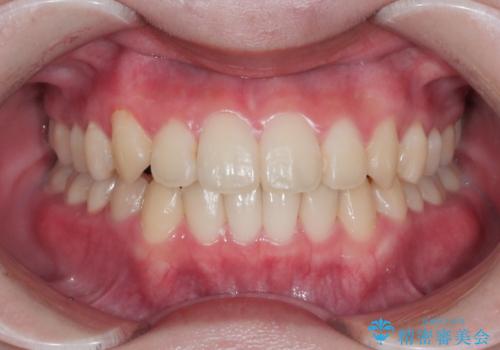

上下のデコボコを治したい インビザラインによる矯正治療